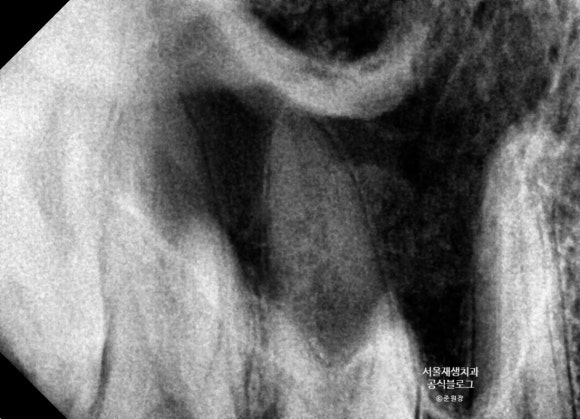

뿌리가 정말 길어서 사진 한 장에 담기지가 않는군요.

머리 부위와 뿌리 부위를 나누어서 촬영했습니다.

보다 이해하시기 편하도록 각 구조물들을 구분하여 표시하였습니다. 아래 사진을 참고해주세요~

하지만 위 사진을 보시면, 긴 뿌리가 잇몸뼈를 넘어서서 상악동까지 올라가고 있지요.